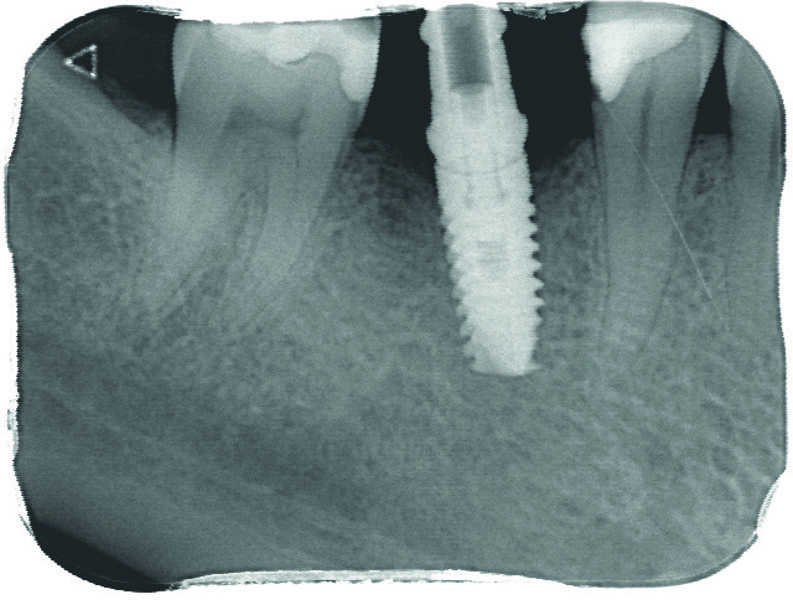

Contrôle radiologique

À l’issue de l’intervention, vérification de la correspondance entre la planification et la chirurgie avec une rétroalvéolaire (Figs. 11 et 12).

Fig. 12 : Radiographie de contrôle postopératoire de l’implant en 46.